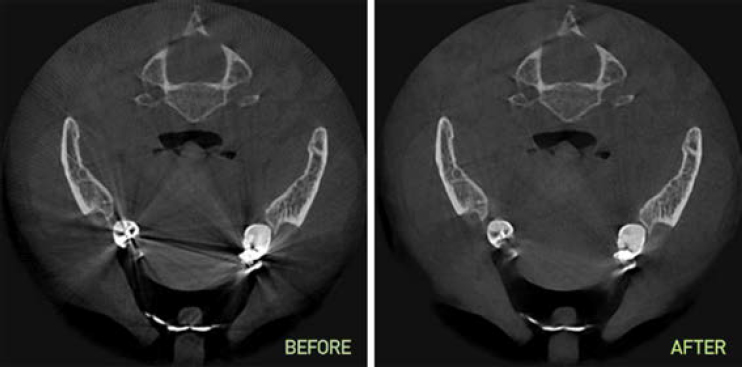

Технология исключения вторичного излучения металлов

SMARF (Smart Metal Artifacts Reduction Function). Обеспечивает превосходную визуализацию костных структур в условиях повышенного вторичного излучения от металлических конструкций в полости рта.

Smarf.jpg